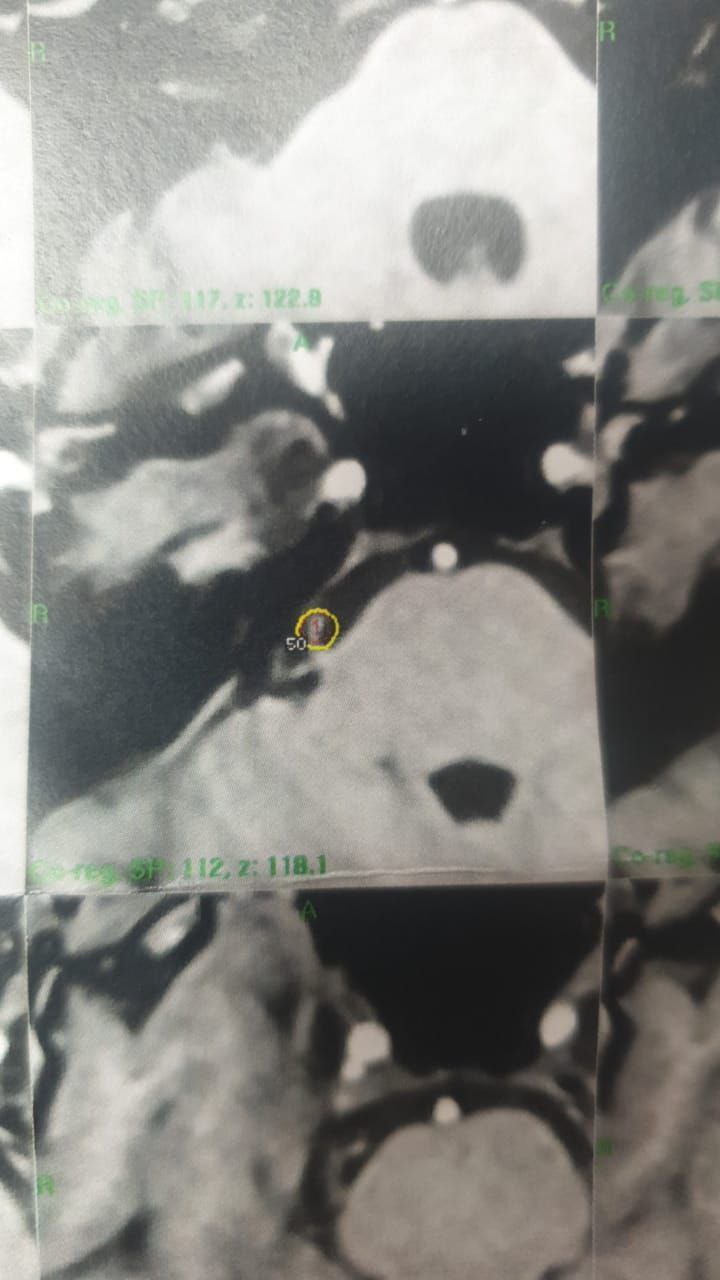

علاج الم العصب الخامس من قبل الأستاذ الدكتور عبد الأمير جاسم محمد